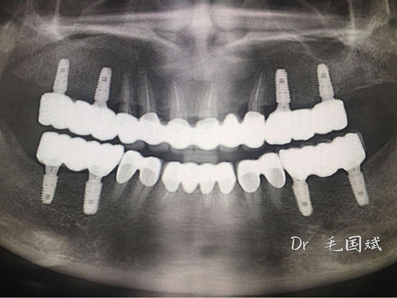

毛國(guó)斌種植病例——群討論分享